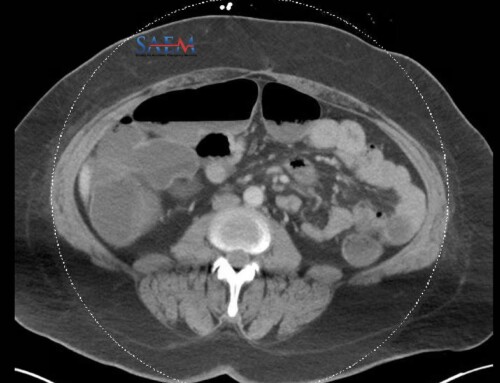

Intraperitoneal insulin pumps

Be aware that some patients with particularly brittle diabetes may actually have intraperitoneal pumps. These pumps are inserted into a subcutaneous pocket, like a pacemaker, and deliver extremely concentrated insulin directly into the peritoneal cavity. While implantation makes the pump less likely to kink or become dislodged, these pumps can present with several significant complications common to all implantable devices, such as pocket erosion and hematoma formation, as well as the rare possibility of frank peritonitis. [5]